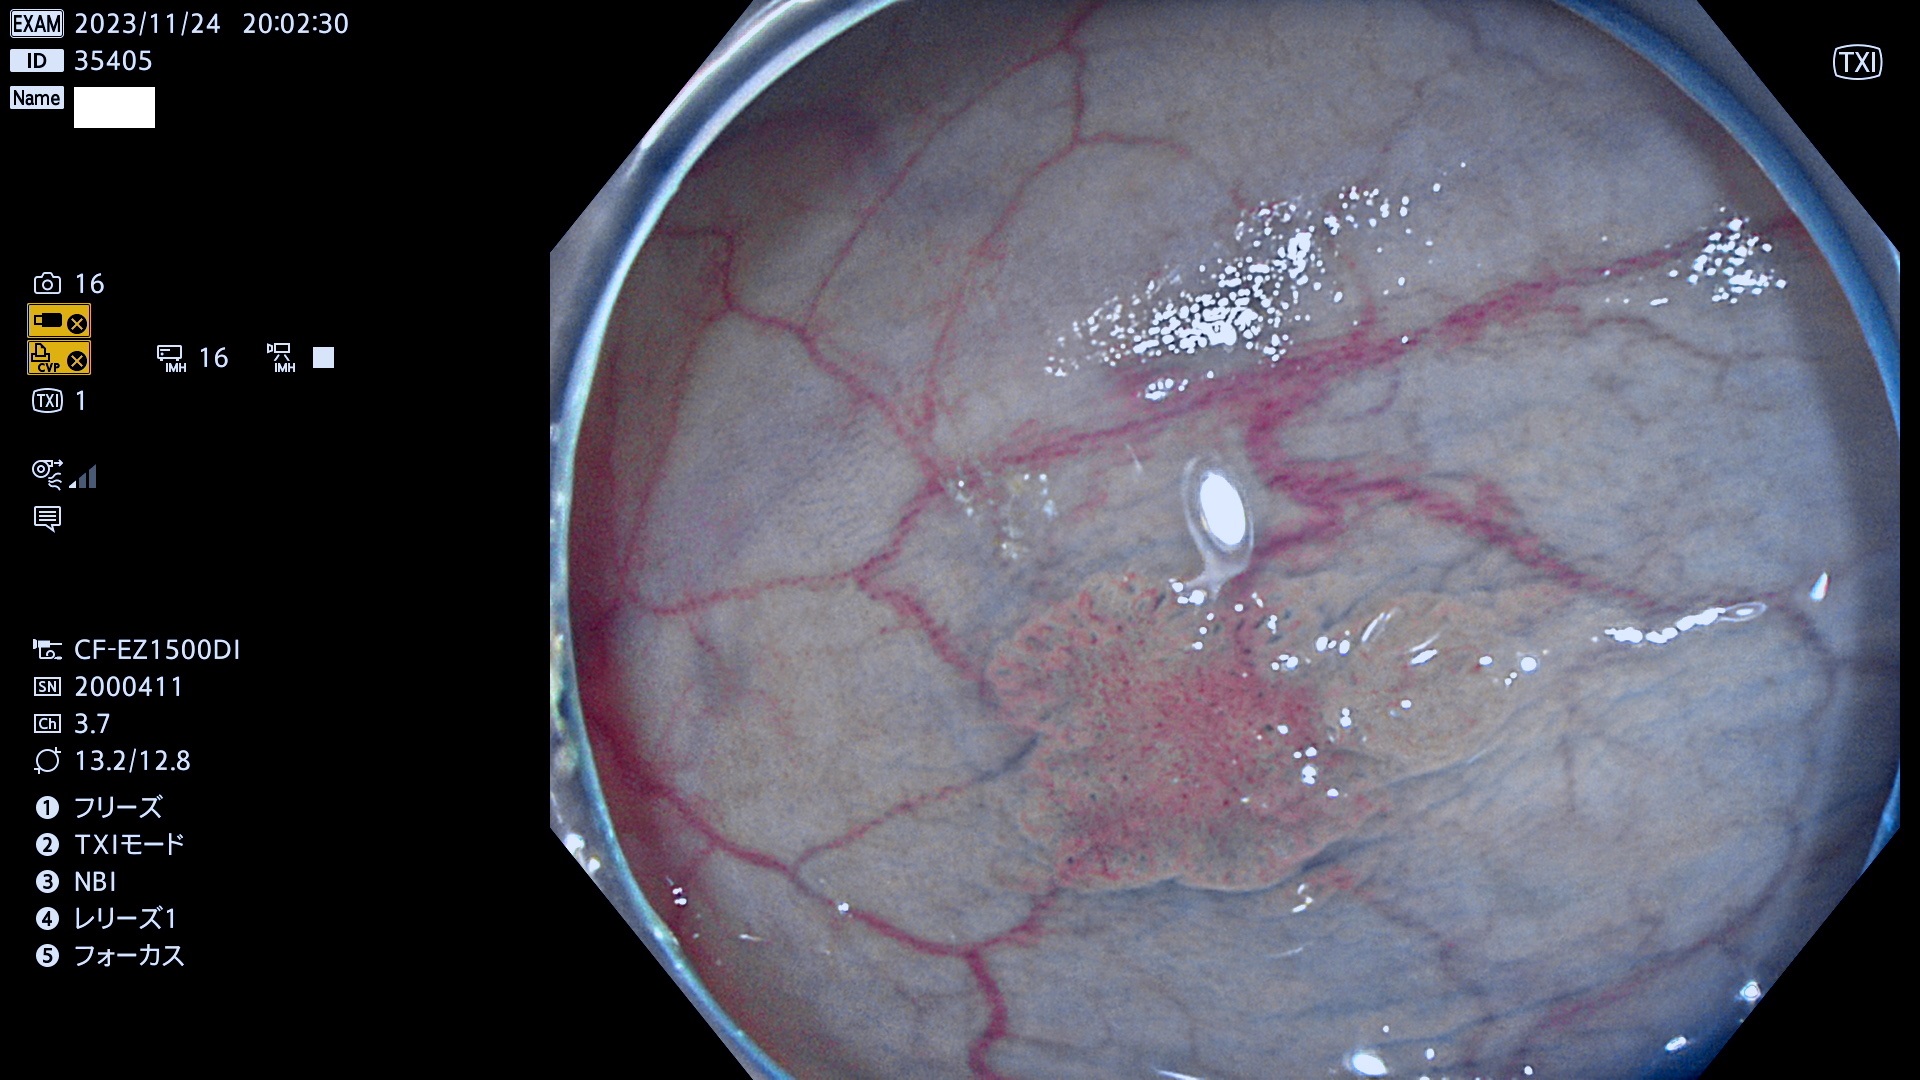

表面型腺腫(Flat Adenoma)の中で、完全に平坦な物をUb、陥凹している物をUcと呼びます。平坦隆起型(Ua)よりも、発見が難しく危険な病変です。このタイプは「内視鏡後・大腸癌の重要犯人」であり、この発見率は「腺腫発見率」よりも、重要な意味があります。

毎週の検査(木・金・土・日)に発見されたUb、Uc型・腺腫を、その週の日曜の夜にUPし1週間、提示します。

抽出の対象期間 2023年11月23日(木)〜11月26(日)の4日間(48件の検査)8件